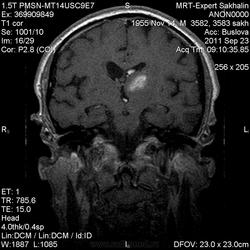

ID:53258

Онмк по геморрагичесому типу с образованием внутримозговой гематомы (подострая аза), прорывом в полость левого бокового и III -го желудочков.

Цель введения контраста наверное для исключения объема. Хотя. Наверное только динамика ответить на данный момент. Надо выносить в заключение весь диагностической ряд. Но больше похоже действительно на зона геморрагического НК. А сосуды не делали? Может имеет место венозное нарушение?

Танюша, не-а, в данном случае не имет место. Классика.

И почему острая фаза?Подострый период.

Да, подострый, не знаю куда я смотрел, что насчитал менее 3 дней.